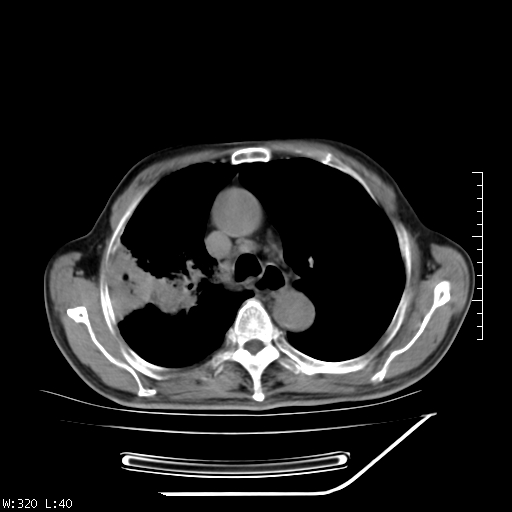

标题: CT23994:男、72、咳嗽、气短两月余,近来消瘦。 [打印本页]

标题: CT23994:男、72、咳嗽、气短两月余,近来消瘦。

右上肺实变,与胸膜关系密切,右肺容积缩小,隆突下淋巴结增大,考虑1 肺结核 2 肺癌

右上肺大片状密度增高影,与胸膜关系密切,内见低密度透亮影,胸膜下可见三角形不张影,左下肺沿支气管走形结节影,纵膈内淋巴结显示。考虑结核并疤痕性不张可能性大,建议穿刺活检,排除肺泡癌。

以下是引用muzi888在2010-1-6 9:43:00的发言:[br]右上肺实变,与胸膜关系密切,右肺容积缩小,隆突下淋巴结增大,考虑1 肺结核 2 肺癌